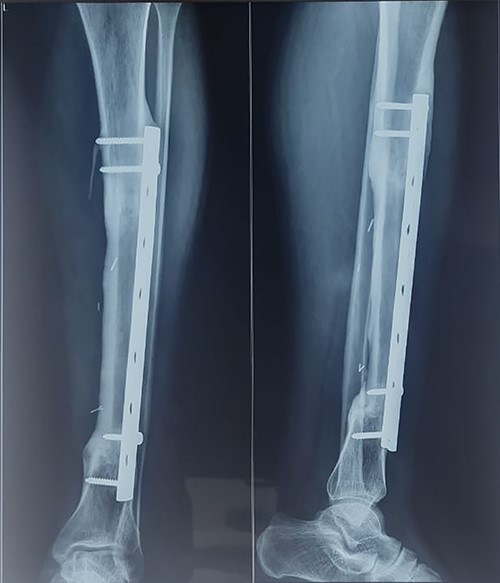

A 33-year-old gentleman presented with slow-growing swelling over the anteromedial aspect of the midshaft of left leg with dull aching pain for 2 years. The swelling was bony hard, 10 cm long and was fixed to the underlying tibia (Fig. 1). Anterior and posterior tibial arteries, sensory and motor functions of the affected legs were intact. Preoperative incisional biopsy report shows multiple epithelial-like cells in a background of fibrous dysplasia, suggestive of adamantinoma. X-ray suggested lytic expansile lesion with multiple septa and sclerotic margins involving the tibia’s diaphysis (Fig. 2). Computed tomography scan showed a cystic expansile lesion with a sclerotic margin obliterating the medullary cavity. Chest X-ray and abdominal ultrasound were normal. The bony defect in the tibia after wide excision of the tumour was 16 cm (Fig. 3) reconstructed with free fibula flap harvested from the opposite leg (Fig. 4). The bone flap was fixed to the tibia with a dynamic compression plate and bicortical screws (Fig. 4). The fibula flap pedicle, peroneal artery and one venae comitantes were anastomosed with the posterior tibial artery and great saphenous vein, respectively. Post-operatively, the flap, flap donor site and recipient’s leg wound healed without complications. Histopathological examination of excised lesion confirmed the diagnosis of classic adamantinoma with margins free of tumour (Fig. 5). After 1 year, there was radiological bone union, evidenced by uninterrupted bony borders between the fibula and recipient tibia bone, obscured osteotomy line at both the junctions and hypertrophy of the transferred fibula as per the bone union criteria by Hsu et al. [3]. The patient started partial weight-bearing in the operated limb after 6 months without any displacement or fracture of the vascularized bone graft. Three years post-surgery follow-up showed good evidence of bony integration and hypertrophy of the bone of the fibula flap, gradually accepting the shape of the tibia without any local recurrence or distant metastasis (Fig. 6). Patient is completely bearing weight on the affected lower limb with good function (Fig. 7).

Intraoperative image with bone defect bridged with vascularized free fibula fixed with dynamic compression plate.